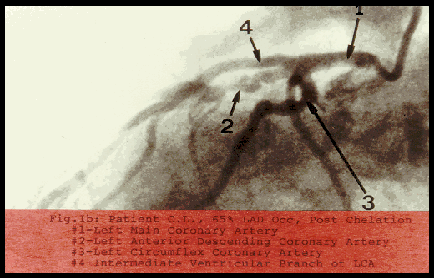

Following a myocardial infarction, a symptomatic 59 year-old male Caucasian was found by coronary arteriography in 1990 to have 100% closure of the left anterior descending coronary artery and 30% stenosis of the right coronary artery. His left ventricle was hypokinetic and exhibited dilatation and abnormal contractility. He refused coronary artery bypass surgery and angioplasty because of risk and instead chose the nontraditional ethylenediaminetetraacetic acid (EDTA) chelation therapy. The disease process, as seen by comparing pre- and post treatment arteriograms in 1990 and 1992, respectively, has been significantly reversed.